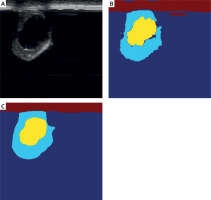

Key region identification using Grad-CAM technology

Grad-CAM was used to visualize the model’s decision-making process. Figure 4 shows that the model focuses on areas with dense plaque accumulation and critical regions of vascular narrowing. Clinical validation confirmed that these highlighted high-risk areas correspond closely with regions targeted in clinical interventions, significantly enhancing the model’s interpretability. This visualization tool not only increases clinicians’ confidence in AI-assisted diagnosis but also provides important feedback for further model optimization.